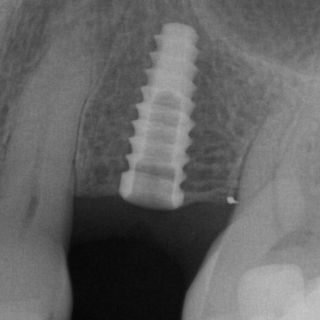

X-rays, or dental radiographs, can help detect and diagnose dental issues early. Two types of x-rays might be recommended during your routine exam. The panorex or full face x-ray is generally recommended every five years. A panorex allows your dentist to visualize the jaw bones, sinuses, roots of the teeth and other head and neck anatomy. Your dentist is trained to detect abnormalities and will let you know if he sees something that requires attention. Bitewing x-rays are generally recommended every 1-2 years. Bitewings can help detect cavities, especially when they are small and in between teeth. Finding cavities when they are small can prevent the need for more expensive dental treatments such as crowns or root canals. Bitewing x-rays also help your dentist visualize the supporting bone around your teeth. Detecting the loss of bone around teeth early is important to maintaining healthy gums.